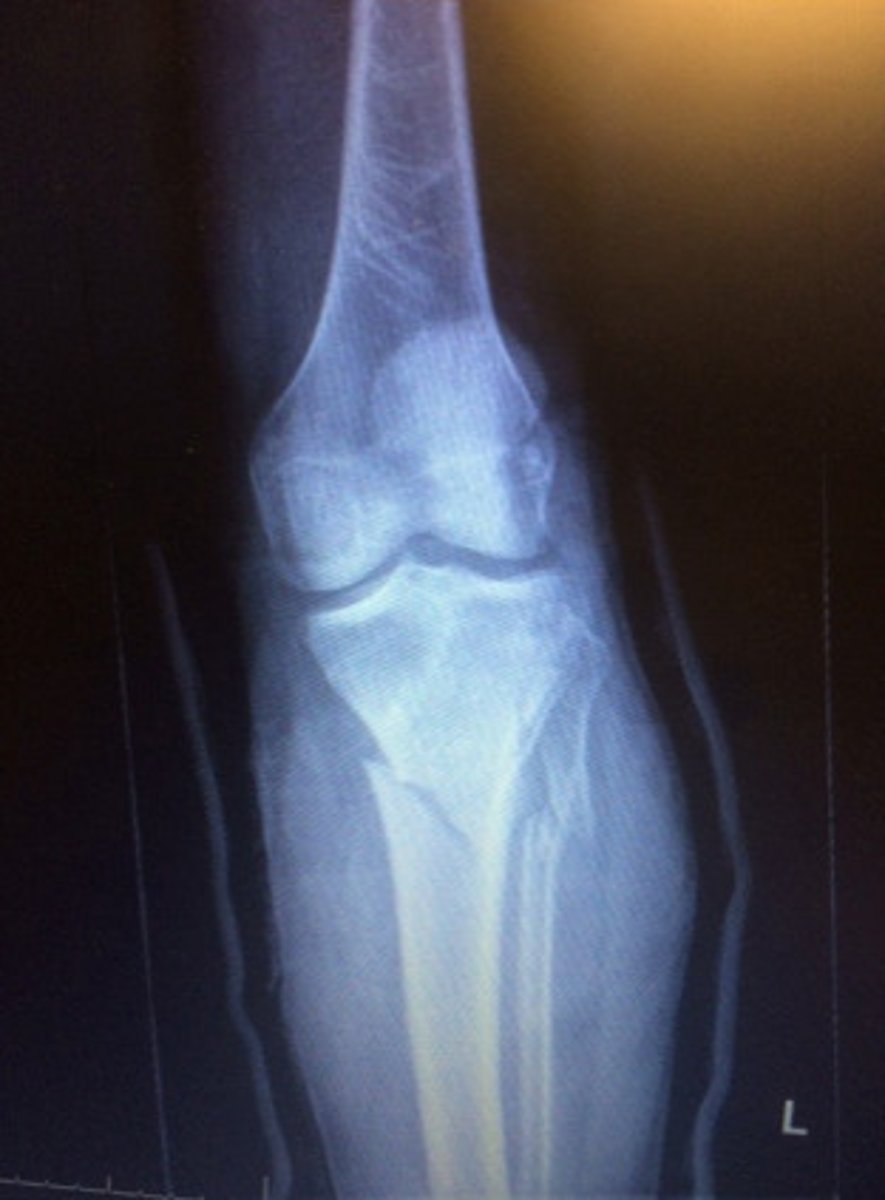

Fracture of the lateral malleolus, medial malleolus, and distal posterior tip of tibia

Trimalleolar fx

Complete fracture of distal fibula, frequently with fracture of medial malleolus

Pott's fx